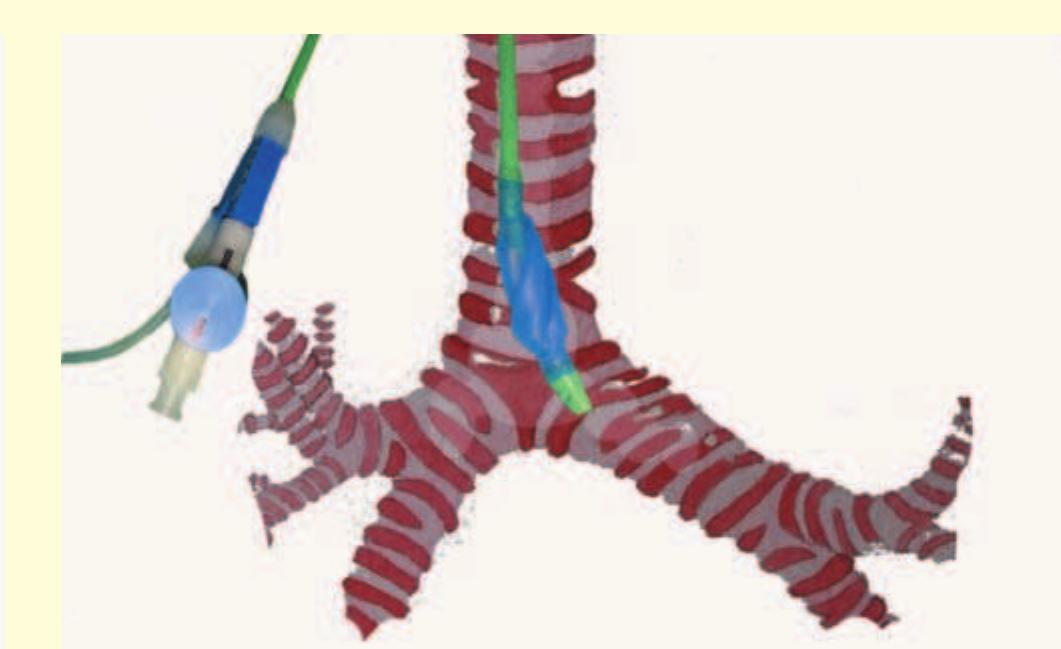

- Once the loop is tightened around the bronchoscope, the endobronchial blocker can be guided to any lobar bronchus (Fig. 12.11).

- Bronchoscopy with the nasal approach is performed and a polyethylene catheter is placed through the instrument channel of the bronchoscope and into the desired airway.